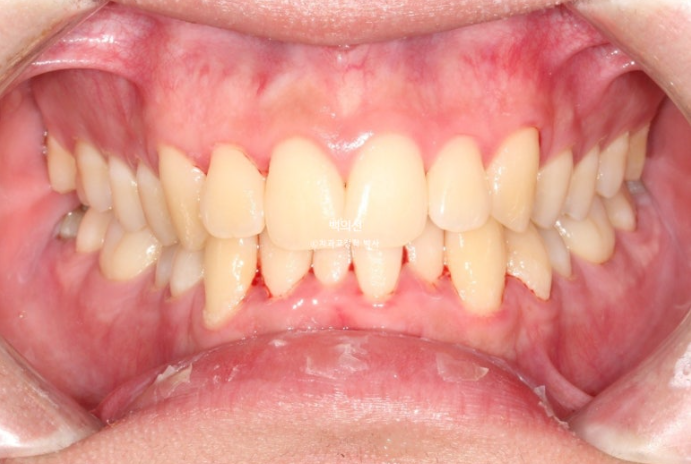

25.02

특히 아래 앞니가 많이 삐뚤하며 작은어금니가 안으로 쓰러져 있습니다.

그러나 어금니 교합관계가 1급으로 좋은 편이고 부정교합의 유형이 치아회전이 많지 않아 14개 장치 안에서 해결가능한 경미한 부정교합에 사용하는 인비절라인 라이트로 충분하여 인비절라인 라이트 권유드렸습니다.